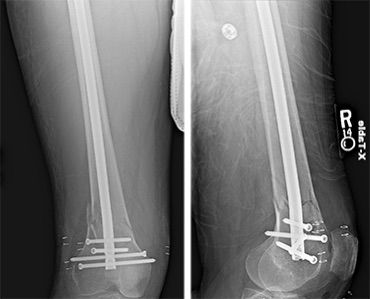

Robotic assisted knee surgery procedure image 2 Robotic assisted knee surgery procedure image 3 Robotic assisted knee surgery procedure image 4 Robotic assisted knee surgery procedure image 5

In Knee Fracture Surgery, this technology helps:

• Map the patient’s anatomy in detail

• Plan exact implant placement or fixation

• Execute surgery with millimeter-level accuracy

3. Cases Requiring Implant Placement

When plates, screws, or joint replacements are needed, robotic guidance helps in:

• Optimal positioning

• Reduced chances of implant failure

• Better long-term outcomes